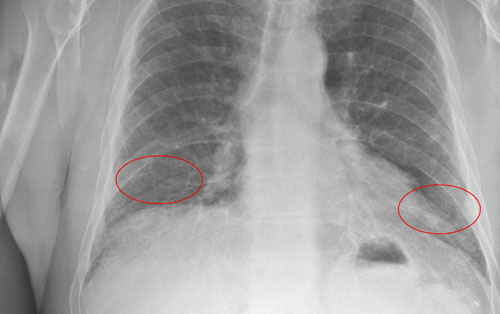

最近,研究者首次找到了治疗致命性肺癌——特发性肺纤维化(diopathic pulmonary fibrosis)的药物。

该病每年在美国发生率大约有8万例,通常患者呼吸困难,3-4年后死亡。医生也对患有这种病症的病人毫无应对策略,唯一能够做的就是缓解病人的咳嗽。